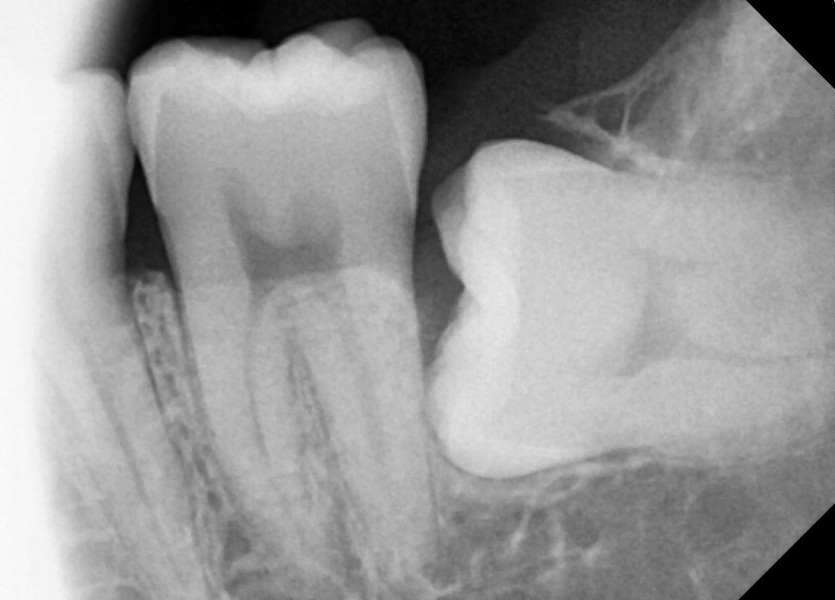

#38 사랑니 발치

구강 외과 전문의가 당일 발치했습니다.